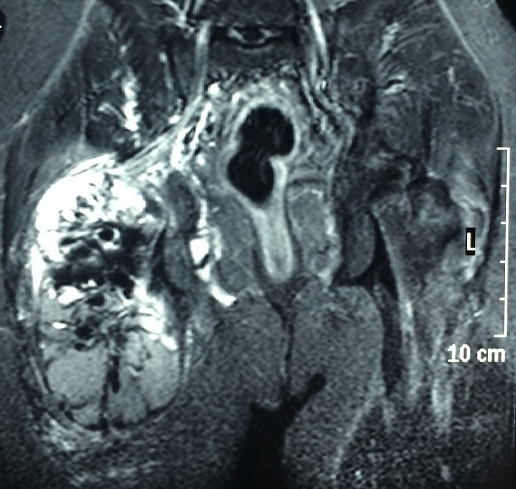

La calcinose tumorale est une affection bénigne rare, qui se caractérise par le dépôt de matériel calcique dans les tissus mous extra-articulaires prenant une forme tumorale. Elle peut être primitive ou secondaire à une insuffisance rénale chronique. Nous rapportons un nouveau cas de calcinose tumorale chez un jeune homme âgé de 27 ans. Ce patient est en insuffisance rénale terminale secondaire à une uropathie malformative depuis 15 ans, traité initialement par dialyse péritonéale puis par hémodialyse. Le patient présentait depuis 5 mois une tuméfaction progressive de la hanche le gênant à la marche. L’examen trouvait une infiltration de consistance pierreuse. Il n’y avait pas de lésion cutanée anormale. La radiographie du bassin mettait en évidence d’importants dépôts calciques diffus dans le tissu souscutané.La scintigraphie osseuse montre une hyperfixation en regard de la hanche. L’imagerie par résonnance magnétique trouvait une calcinose tumorale de la face postérieure de la racine de la cuisse mesurant 14x13x12 cm bien limitée hétérogène avec fine prise de contraste périphérique et des septas, situé au niveau du muscle grand fessier, grand adducteur et prenant la partie proximale du tendon conjoint du biceps fémoral et semi tendineux. Cette masse arrive au contact du nerf sciatique sans engagement du derrier. La biologie trouvait une calcémie à 2,33 mmol/L, phosphorémie à 3,1 mmol/L, parathyroide hormone (PTH) à 770 ng/L et créatinine à 977 mol/L. Une indication opératoire était proposée mais refusé par le patient.